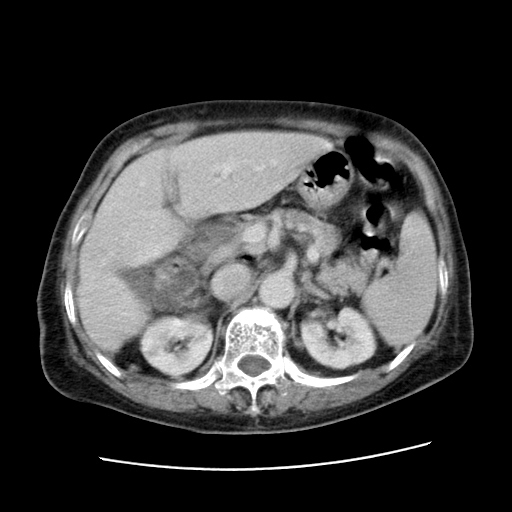

女,77.无不适

肝脏变异、异位胆囊,肝右叶肝内胆管结石并肝内胆管扩张。

肝右叶肝内胆管结石并肝内胆管扩张。

肝右叶肝内胆管结石并肝内胆管扩张

胆总管扩张

肝右叶肝内胆管结石并肝内胆管扩张。胆总管下段梗阻,考虑壶腹部占位。

右侧肝内胆管局限性扩张,其内密度不均匀,扩张的胆管壁增厚,考虑肝内胆管炎合并结石可能性大